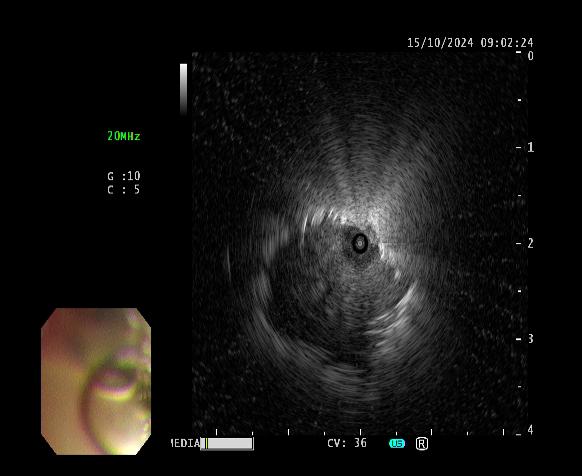

患者女性,因“气短1月”来门诊就诊,为明确诊断进一步治疗,收入乐鱼在线登录入口。入院后完善相关检查,胸部CT示左肺上叶前段高密度灶,与家属充分沟通后,决定为患者行超声支气管镜检查。主任医师吴水淼与主管护师薛冬冬为患者行气管镜检查,镜下示:双肺支气管均未见明显异常,结合CT给予超声探查,于左肺上叶前段亚支探及偏心异常回声区,由于亚支位置较高且管腔较窄,活检钳无法到达,给予冷冻肺活检。此次检查过程顺利,成功获取2块活检标本,活检病理结果提示为粘液腺癌。